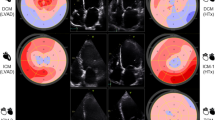

In semiquantitative perfusion analysis, time-signal intensity curves of motion corrected perfusion sequences were generated for each myocardial segment using semiautomated tracking of the endocardial and epicardial borders with manual correction to exclude artifacts. Corresponding time signal intensity curves were derived for each myocardial segment, and the maximal slope of these curves was reported for each of the 16 myocardial segments. This analysis was repeated for rest perfusion imaging and a myocardial perfusion reserve index (MPRI) (stress/rest slope) calculated for each segment. Baseline correction was applied on the rest perfusion sequences to account for remaining gadolinium contrast signal from the stress sequences performed first. An MPRI below 2 was considered abnormal17. Figure 2 shows an example case.

Semiquantitative analysis of MPRI. A case example of a 58 years old patient with hypertrophic cardiomyopathy and septal thickness of 2.7 cm, panel A. Panels B and C show derivation of MPRI at rest and stress respectively. Red arrows highlight segments with reduced flow at stress. Panels E and F show enhancement curves of myocardial segments at rest and stress respectively, with the arterial input function in orange. Panel D shows a polar plot with reduced MPRI measures in the septum. MPRI, myocardial perfusion reserve index; LVOT, left ventricular outflow tract. Patient consent for publishing anonymized figure was obtained.